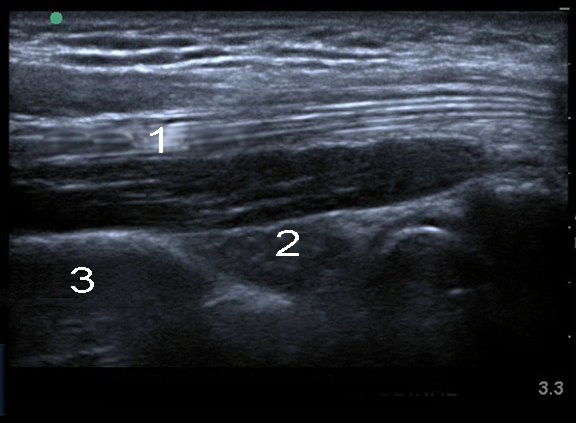

Imagen del tendón del tríceps del codo

Tendón del tríceps

Cuerpo adiposo

Húmero posterior